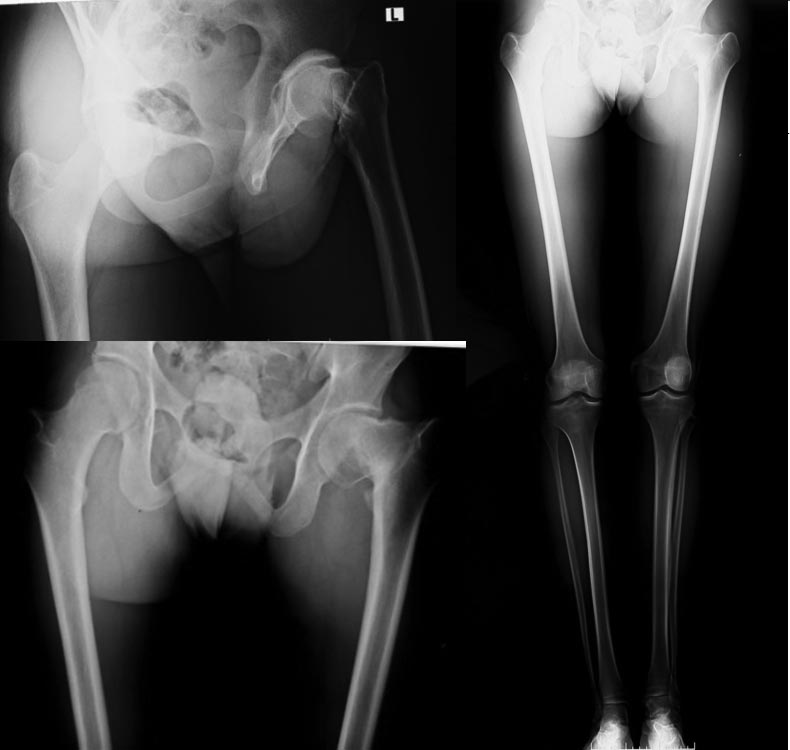

Пациент 18 лет травма в 13 летнем возрасте, остеоэпифезиолиз шейки

бедра, лечится консервативно сейчас. Переелом сросся, беспокоят

периодически не очень интенсивые боли при нагрузках. Беспокоит

укорочение - 4 см, Что делать протез? Остеотомия (какая?) удлинить

голень? Корректно ли поставить диагноз постравматическая koxa vara?